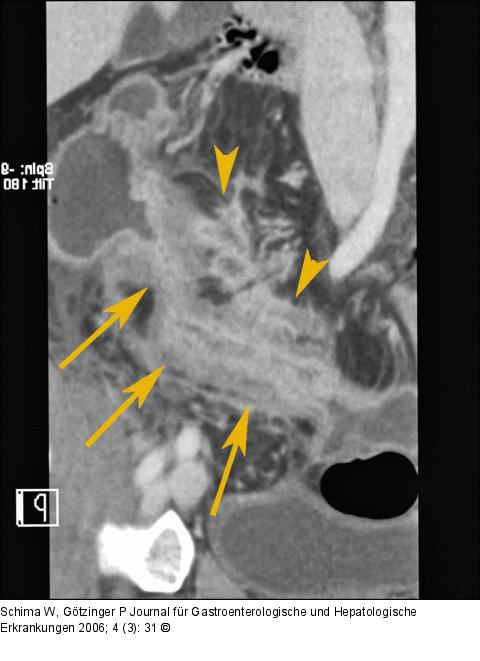

Abbildung 3: Neoterminales Ileum Die gekurvte Rekonstruktion (CPR) entlang des Darmes zeigt genau die septierten Abszesse (Pfeilspitzen) nahe dem neoterminalen Ileum (Pfeile). |

Die gekurvte Rekonstruktion (CPR) entlang des Darmes zeigt genau die septierten Abszesse (Pfeilspitzen) nahe dem neoterminalen Ileum (Pfeile). |